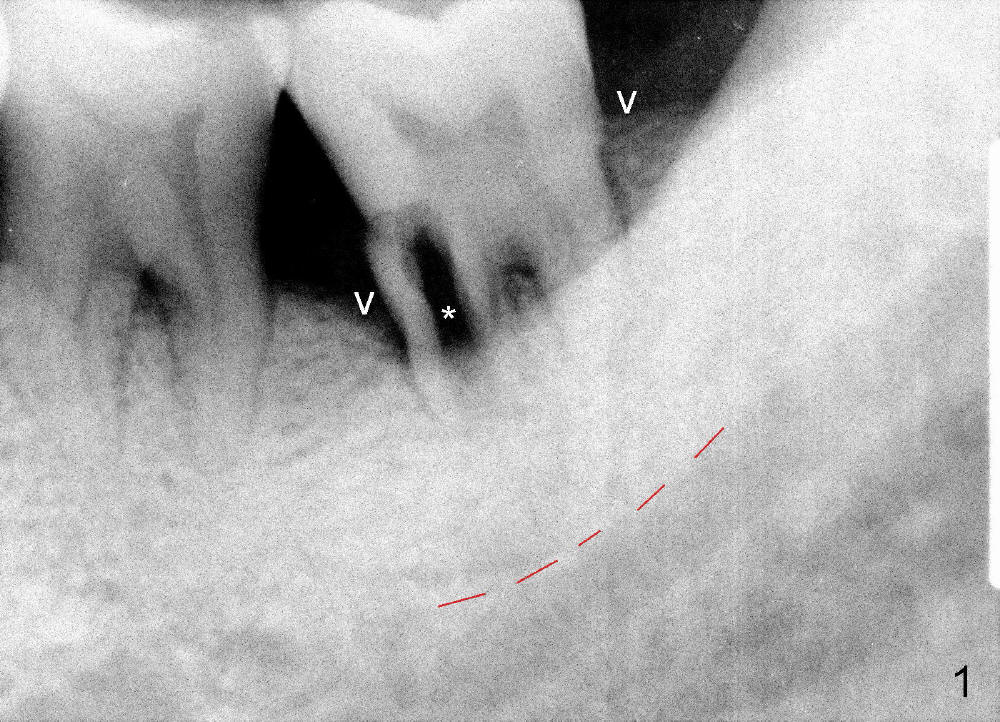

A 51-year-old man has generalized chronic periodontitis. The mesial root of #18 has vertical fracture (Fig.1*) with infection. The patient agrees extraction (Fig.2) and immediate implant. The septum is thin. The pilot drill drops into either the mesial (Fig.3) or distal sockets. Furthermore it is difficult to control pain probably due to severe infection (Fig.2 >: mesiobuccal erythema and edema). Repeated local infiltration does not alleviate pain associated with drilling. Block anesthesia has to be administered (one carpule of 2% Lidocaine with 1:100,000 Epinephrine). Damage to the inferior alveolar nerve (Fig.1 red dashed line) increases. On the other hand, osteotomy through the socket of the tooth with periodontits is easier because of shallow socket. Retraction of the buccal gingiva can reveal the bottom of the socket. We will increase the depth slowly until a tap obtains initial stability. The worst scenario is that active hemorrhage from the socket bottom is encountered initially. The nerve injury can be reduced minimally.

Now where to initiate osteotomy? Since the mesial crest is much lower than the distal (compare arrowheads in Fig.1), placement of an implant in the mesial socket is a good approach, whereas placement in the distal socket is not good for restoration (cantilever). The thin septum is slippery to drill penetration. What should we do?

How about flatten the septum (Fig.4 white lines; from inset A (post extraction) to B)? When the septum is level with the mesial and distal sockets, a drill easily penetrates the middle of the socket (Fig.3 inset C). With strict control of depth, the osteotomy increases until a 6x14 mm tap gets initial binding to the socket (Fig.5: depth 11 mm). After increase in the depth by 1-2 mm, PA is taken with a 7x14 mm tap (Fig.6). There is a gap that the tap or the corresponding implant can engage further (between arrowheads). After increase in the diameter in the bottom of the osteotomy, a 7x11 mm implant is placed with insertion torque between 45 and 50 Ncm; the threads of the implant have tight contact with the bone (Fig.7). With the large diameter implant, the socket opening is closed without too much tension (Fig.8). The wound is protected with perio dressing. Postop there is no paresthesia. Pain is controlled by Hydrocodon/Acetaminophen. A long acting local anesthetic (Marcaine) should have been used immediately postop. Next morning, the patient is pain free. A short implant should be used in a critical area such as the lower 2nd molar where the inferior alveolar nerve is nearby. However, the implant is found unstable 1 month postop.